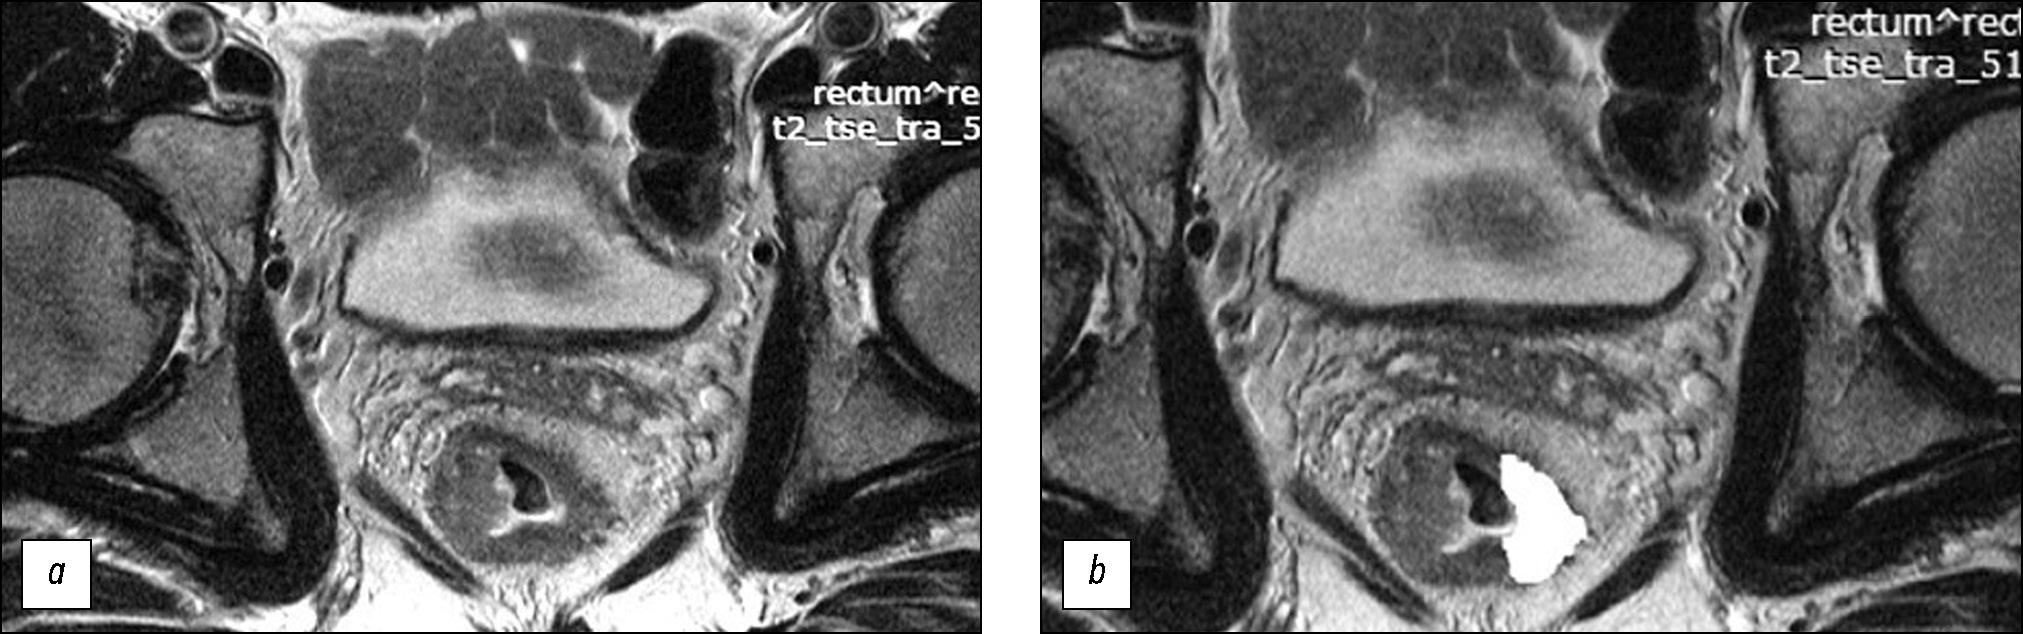

基于直肠癌患者初诊分期时获得的肿瘤加权T2核磁共振图像的纹理分析预测新辅助放化疗的效果

摘要

论证。为了预测局部晚期直肠癌对新辅助放化疗的反应,最近人们在寻找潜在无创生物标志物方面一直在做着巨大的努力。

研究目的 — 评估局部晚期直肠癌在原发加权T2图像上的纹理特征,将其作为预测标准新辅助放化疗效果的潜在因素,并在此基础上开发一套预测此类治疗效果的系统。

材料和方法。在回顾性研究中接受新辅助放化疗综合治疗的局部晚期直肠癌患者(n=82)被分为训练样本(n=58)和对照样本(n=24)。在肿瘤中心水平使用方向垂直于肠壁的高分辨率原始加权T2图像,用于纹理分析。纹理分析基于灰度级共生矩阵(GLCM),借助MAZDAver计算机程序执行了二阶统计法。 4.6和11个纹理参数的计算。在训练样本中进行手术制剂形态学评估后,查明治疗有反应(预后良好组)和无反应(预后不良组)患者组的纹理分析参数的真实差异,并在此基础上创建评估新辅助放化疗效果的评分系统。系统在对照样本上进行测试确定诊断效率的参数。

结果。在训练样本的预后良好组和预后不良组中找到分离点,其五个纹理参数上存在真实差异:AngScMom(p=0.021)、SumofSqs(p=0.003)、SumEntrp(p=0.003)、Entropy(p=0.038)和 SumVarnc(p=0.015),在创建评分系统时排除了 Entropy,因其与 SumEntrp相比有很强的直接相关性,最低的AUC, 以及与SumofSqs相比重现性低。反应预测评分系统的诊断效率在训练样本中的灵敏度、特异性、阳性预测能力和阴性预测能力分别为 72%、69%、70% 和 71%,相应的在对照样本中分别为 80%、64%、62% 和 82%。曲线下面积在训练样本中为 ROC 为 0.77,在对照样本中为 0.72。

结论。对局部晚期直肠癌患者原发肿瘤T2-VI的纹理分析可以预测诊断效率适中的新辅助放化疗效果,表明这个方向的进一步研究的前景性。